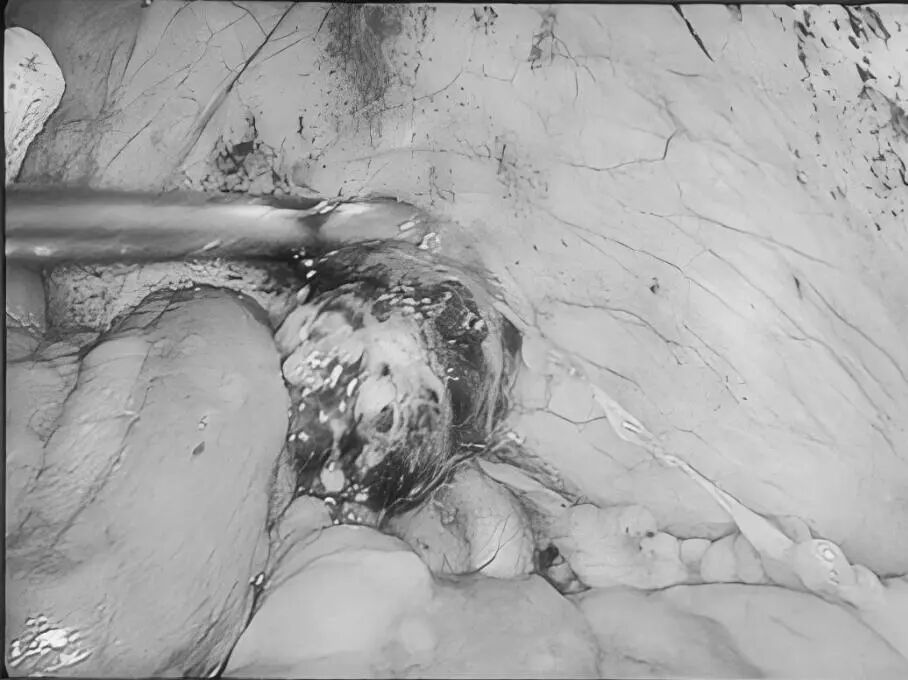

直肠脱垂是指直肠壁的一部分或全层向下移位,最终可能脱出肛门外的疾病。它并非肿瘤,但在老年人、多次分娩的女性、长期便秘或慢性咳嗽等腹压增高人群中较为常见。 【关键诱因与表现】 直肠脱垂主要因盆底肌肉、韧带等支撑结构松弛,加之长期腹压增高(如用力排便、慢性咳嗽、排尿困难)诱发。患者常感肛门坠胀或异物感,典型表现为排便或久站后有柔软肿物自肛门脱出,初期或可自行缩回,后期常需手法复位,并可伴排便困难、不尽感、肛门黏液或血性分泌物、潮湿瘙痒,严重者可能出现排便控制困难。 【治疗选择因人而异】 保守治疗(轻度或早期): 核心是消除诱因: 积极改善便秘(高纤维饮食、充足饮水、必要时遵医嘱用药)、控制咳嗽、解决排尿困难。 生活方式调整: 避免久蹲、久站、负重及用力排便。 盆底肌锻炼(凯格尔运动): 坚持锻炼有助于增强盆底支撑力。 及时复位: 轻柔地将脱出部分复位,防止卡住肿胀。 手术治疗(中重度或保守无效): 当脱垂严重影响生活、难以复位、反复出血或出现排便失禁等情况时,医生会评估手术的必要性。 手术目标是修复薄弱的支撑结构,将直肠固定在正常位置。有多种手术方式(包括微创方法),医生会根据个体情况选择最合适的方案。 【重在预防与管理】 预防的关键在于减少腹压增高因素: 1.保持大便通畅,避免用力排便。 2.积极治疗慢性咳嗽、前列腺增生等导致腹压增高的疾病。 3.坚持规律进行盆底肌锻炼。 4.维持健康体重,避免长期重体力劳动。 直肠脱垂虽然带来不适,但通过及时就医、明确诊断并接受规范治疗(包括生活方式调整和必要的医疗干预),多数患者的症状可以得到有效控制,生活质量显著提升。如有相关疑虑,建议咨询肛肠专科医生。 注:部分图片来源于网络,如有侵权,请联系删除。 贵州航天医院普外科专家简介 高大勇 普外科(肛肠外科)学科带头人、名誉主任,主任医师、教授 临床擅长:对中西医结合诊治肛肠学科各种常见病、多发病及疑难杂症等具有丰富的临床经验。 原遵义市第一人民医院(遵义医科大学第三附属医院)、遵义市中医院肛肠科主任。中华中医药学会肛肠分会常委,全国中医肛肠学科名专家,中国健康促进与教育协会肛肠分会常委,中国康复医学会肛肠疾病康复专业委员会常委,中国民间中医医药研究开发协会肛肠分会副秘书长,中国医师协会中西医结合肛肠医师专业委员会常委,国家二级心理咨询师,贵州省第一批中医名医工作指导老师,遵义市名中医,遵义市肛肠学会会长,遵义市肛肠质控中心名誉主任,遵义市中西医结合学会名誉会长,遵义市健康科普专家,原贵州省中西医结合学会肛肠分会副主任委员、贵州省中医肛肠质控中心副主任、遵义市医学会医疗鉴定委员会专家、遵义市卫生系列高评委。发表论文30余篇,主编和参编医学著作5本,主持省级科研课题2项、市级科研课题2项、院级科研课题1项。 梁 跃 中共党员,普外科党支部书记、主任,主任医师 临床擅长:对普外科各类肿瘤手术具有丰富的临床经验。 毕业于遵义医学院,遵义市医学会小儿外科学分会常务委员,遵义市肛肠协会理事,遵义市医学会核医学分会(第二届)委员会委员;荣获第三期“黔医人才计划”优秀学员称号;主持市级课题1项,完成省级课题1项,在国内各类刊物上发表论文10余篇。 钱科洪 民盟盟员,普外科副主任医师 临床擅长:从事普外科临床工作30余年,对各类普外科疾病的诊治、乳腺、甲状腺、胃十二指肠、结直肠等疾病及疑难杂症具有丰富的临床经验。 毕业于遵义医学院临床医疗系,2009年前往中山大学附属第一医院微创外科进修学习,在国内各专业期刊发表论文数篇。 贵州航天医院普外科简介 基本情况 贵州航天医院普外科成立于1968年,前身属于航天部O61基地3417医院外一科,1998年3417医院、3427医院合并后更名为普外科,下设胃肠外科、肛肠外科2个亚专业科室,拥有在全市较为先进的专科设备和技术,是中国疝病专科联盟单位,贵州医科大学附属医院胃肠外科专科联盟单位。开放床位40张,配备医护人员21人。 专科特色 普外科致力于胃肠及肛肠疾病的外科临床诊治及科研,以腹腔镜微创外科技术为本,形成以快速康复治疗胃肿瘤、结直肠肿瘤、小肠肿瘤、直肠脱垂、肥胖病、急腹症、各类疝、痔、瘘等专科特色,同时注重胃肠疾病尤其是结直肠恶性肿瘤的基础研究和临床转化研究,总体诊断和治疗水平在区域同级医院居于领先水平。 开展手术:腹腔镜下胃癌根治术,腹腔镜下袖状胃切除术,腹腔镜下胃肠道间质瘤切除术,腹腔镜下结、直肠癌根治术,胃癌、结直肠癌的精准治疗,腹腔镜下小儿疝气、成人疝修补术,腹腔镜下阑尾手术,内痔的硬化注射治疗及痔疮的微创治疗:ATH、PPH、TST,直肠脱垂的各种手术治疗,难治性伤口VSD技术,鼻胃肠管、肠梗阻导管置入术,肛肠术后间歇性导尿技术,并引进了中医适宜技术,也为各种化疗患者提供输液港安装,提高患者就医体验。 腹腔镜下腹股沟疝 无张力修补术 腹股沟疝里金斯坦(Lichtenstein)手术 PPH微创术治疗环状混合痔 黏连性或炎性肠梗阻-肠梗阻导管 腹腔镜袖状胃切除 腹腔镜阑尾切除术 腹腔镜阑尾肿瘤切除术 腹腔镜下结肠癌根治术 诊疗范围 胃肿瘤、结直肠肿瘤、小肠肿瘤、肥胖症、各类急腹症、腹部外伤、腹壁疝、便秘、直肠脱垂、痔疮、肛瘘、肛裂等胃肠、肛肠外科疾病。 END